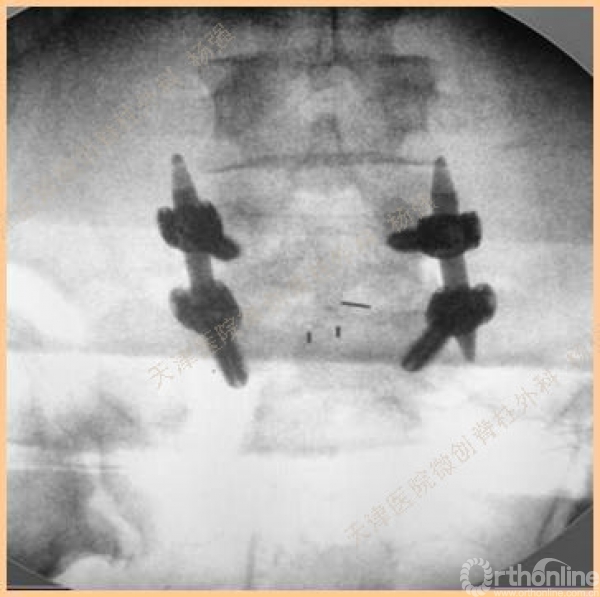

腰5椎体前滑脱I-II°,峡部裂,动力位显示腰5-骶1节段明显失稳

CT、MRI示:腰5椎体前滑脱,腰5/骶1水平间盘突出,腰5双侧椎弓峡部裂